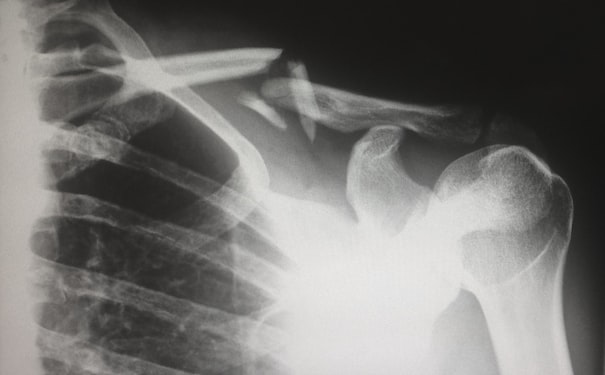

1. 外科手术:医学模型视频可以为外科手术提供多种不同类型的视频,如心脏手术视频、腹腔镜手术视频等,帮助医学教育机构提高外科手术实践教学水平。